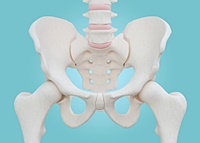

고관절은 골반을 지탱하는 중요한 관절로, 근육과 힘줄로 구성되어 있습니다. 학계에서는 이를 엉덩이 관절이라고 부르며, 신체의 하중을 지탱하는 중요한 역할을 합니다. 고관절은 우리가 정상적으로 서고 움직일 수 있도록 도와주며, 달리기, 점프, 무거운 물건을 들 때 최대 체중의 2~10배에 달하는 압력을 견딥니다. 따라서 적절한 관리가 필요합니다. 오늘은 고관절에서 나타날 수 있는 고관절 통증 증상 10가지에 대해 알아보겠습니다.

고관절 통증의 주요 원인은 퇴행성 질환으로, 나이가 들면서 관절 손상이 발생하는 것입니다. 고관절 자체의 구조적 문제, 주변 근육과 인대의 문제, 척추와 골반 문제 등 다양한 원인이 있습니다. 퇴행성 고관절염, 대퇴골두 무혈성 괴사, 대퇴골 경부 골절, 퇴행성 관절염, 급성 활액막염 등이 주요 원인입니다. 이러한 질환들은 심각한 합병증을 유발할 수 있어 빠른 치료가 필요합니다.